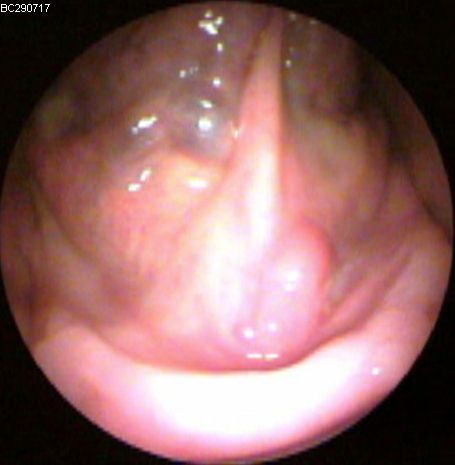

JFC Edema de Reincke